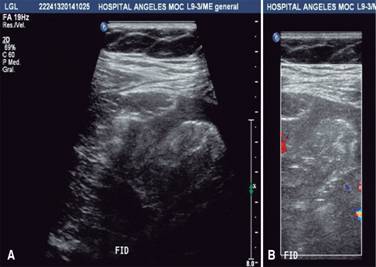

Se presentó al Servicio de Urgencias con los siguientes signos vitales: FC, 80 lpm; FR, 21 rpm; TA, 120/80; T, 37 oC; refería cuadro de dolor abdominal de aparición súbita con aproximadamente siete horas de evolución, constante, en la fosa iliaca derecha (FID), EVA 7/10, irradiado a la región lumbar ipsilateral, vómito en una ocasión de contenido gástrico, sin fiebre, acompañado de náusea y sangrado transvaginal de aproximadamente 15 cm3; negó ingesta previa de medicamentos, así como la presencia de exacerbantes y atenuantes. A la exploración, se encontró abdomen globoso a expensas de panículo adiposo, peristalsis presente, disminuida en la FID; abdomen blando, resistencia muscular voluntaria, doloroso a la palpación superficial, media y profunda en la FID; hiperbaralgesia e hiperestesia dudosas de predominio en la FID; no se palpó crecimiento uterino; dolor en punto de McBurney (+), VonBlumberg (+), Rovsing (-), talopercusión (+). Laboratorios de ingreso, con hemoglobina de 13.2, hematocrito de 38, leucocitos de 26.9, segmentado 95, BUN 10.2, urea 22.1, creatinina 0.58. El USG ginecológico reportó útero gestante de 12.0 × 8.2 × 7.4 cm en sus ejes longitudinal, AP y transversal. En la cavidad endometrial se observaron dos sacos gestacionales de localización normal y apariencia viable, compatibles con embarazo gemelar intrauterino; fondo de saco de Douglas con líquido libre; fosa iliaca derecha en topografía del ciego, se observó asa de paredes levemente engrosadas y peristalsis ausente, líquido libre alrededor; no se pudo descartar proceso inflamatorio apendicular (Figura 1). Se programó apendicectomía laparoscópica; se halló hemoperitoneo de 250 cm3, salpinge derecha aumentada de tamaño, rota y con sangrado activo compatible con embarazo ectópico roto, coágulo organizado en la FID; útero grávido aumentado de tamaño, anexo izquierdo normal, ovario derecho con cuerpo lúteo. Se realizó salpingectomía derecha, evacuación de hemoperitoneo y lavado de cavidad; se colocó drenaje tipo Blacke 19 French (Figura 2); postoperatorio con diagnóstico de embarazo heterotópico roto derecho (Figura 3). La paciente pasó compensada a la Unidad de Cuidado Postoperatorio. Al día siguiente, drenaje con gasto de 85 cm3 serohemático; se realizó un USG obstétrico que reportó vitalidad y viabilidad de los productos fetales intrauterinos (Figura 4). Cuarenta y ocho horas posteriores al procedimiento quirúrgico, se retiró el drenaje y fue dada de alta por los Servicios de Ginecología y Cirugía General. El nacimiento de dos productos, uno del sexo masculino y otro femenino, se llevó a cabo a las 35 SDG mediante cesárea; la indicación de la misma fue preeclampsia desarrollada durante el embarazo. No se presentaron complicaciones durante el procedimiento.

Figura 1: (A) USG abdominal. En la FID, en topografía del ciego, se observa un asa de paredes levemente engrosadas y peristalsis ausente, así como líquido libre alrededor. (B) Tras la aplicación del Doppler color, no se observan reforzamientos anormales; no es posible descartar proceso inflamatorio apendicular. Ovario derecho, con volumen aproximado de 18 cm3.